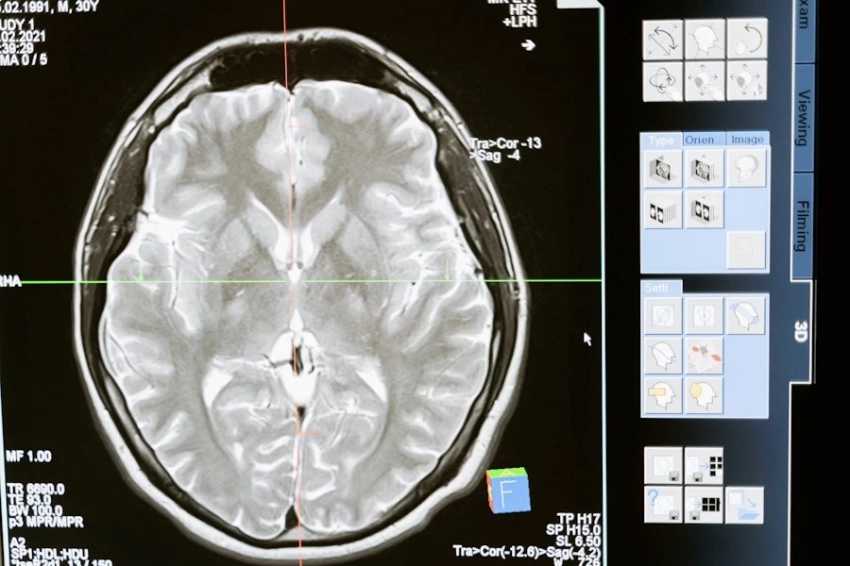

В рамках исследования авторы сравнили сканирование мозга пожилых людей, у которых в возрасте 30 лет отмечалось высокое давление и тех, кто проблем в молодости с давлением не имел. В итоге они установили, что у первой группы мозг имел меньшее количество серого вещества в областях лобной доли и теменной коры, а именно эти области мозга важны для когнитивных процессов, среди которых внимание, память и способность принимать решения. Также они важны для пространственного восприятия и сенсорной обработки. Белое же вещество также в общем уступало по целостности. Как отмечают ученые и тот, и другой фактор напрямую связаны с учеными.

Всего же ученые в своей работе использовали данные двух исследований, посвященных здоровому старению. Окончательная выборка состояла из 427 человек, прошедших обследование здоровья в период с 1964 по 1985 год, а также МРТ в период с 2017 по 2022 год.